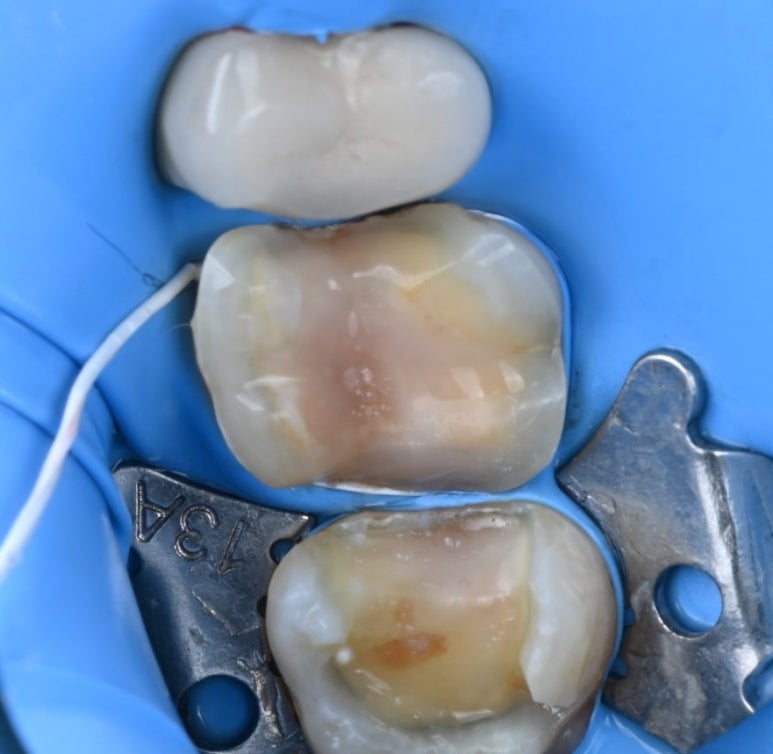

이보다치과에서는

보철물의 수명을 결정짓는

'접착' 단계에서 절대 타협하지 않는 원칙이 있습니다.

러버댐(Rubber Dam) 장착

치료 부위를 입안의 습기와 침으로부터

완벽하게 격리합니다.

세라믹 접착제는 수분에 매우 민감하기 때문에,

러버댐 없이 진행하는 접착은

보철물의 탈락이나 2차 충치의 원인이

될 수 있습니다.

25.11.11 러버댐 장착 후 레진 코팅을 시행한 모습

레진 코팅(Resin Coating)

본을 뜨기 전, 노출된 상아질을

레진으로 얇게 코팅하여 신경을 보호하고

접착력을 극대화합니다.

이 과정을 거치면 치료 후 시린 증상이 현저히 줄어듭니다.